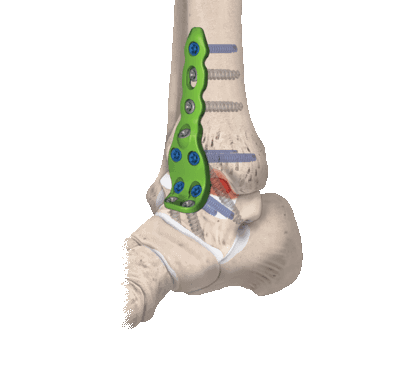

Как устроены современные эндопротезы голеностопа

Ранее пациентам устанавливали металлические протезы, которые плохо держались на цементе и не давали нужного результата. Сегодня хирурги-ортопеды используют только протезы третьего поколения, которые полностью срастаются с костью и надежно фиксируются, обеспечивая суставу естественную биомеханику.

- На таранную кость надевают специальную металлическую крышку.

- Поверхность большеберцовой кости накрывают металлической пластиной.

- Третий компонент протеза - это свободно двигающийся полиэтиленовый сердечник.